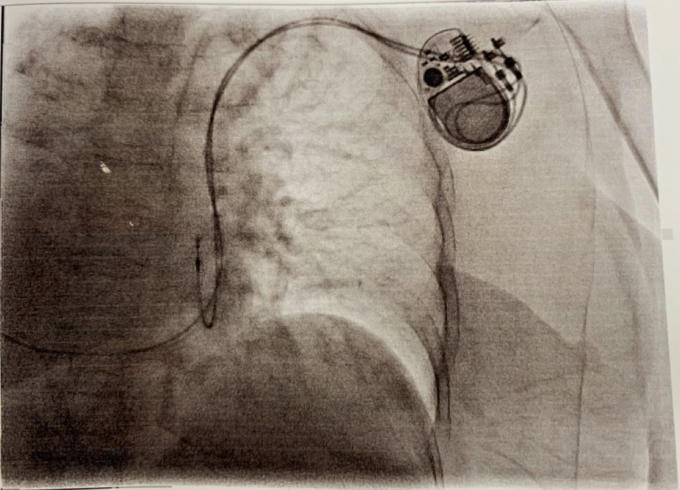

Các bác sĩ tiến hành đo điện tâm đồ, chụp X-quang ngực và siêu âm tim và phát hiện bà X. có tình trạng đảo ngược phủ tạng hoàn toàn, rối loạn nhịp tim chậm, Block AV độ III. Nhịp tim của bệnh nhân chỉ 35 lần/phút.

Bà X. được can thiệp, đặt máy tạo nhịp tim tạm thời cấp cứu qua đường tĩnh mạch trước khi đặt máy tạo nhịp tim vĩnh viễn.

Máy tạo nhịp tim vĩnh viễn được đặt vào cơ thể bệnh nhân.

"Cái khó của ca bệnh này là tim của người bệnh nằm ở bên phải, nên các thao tác rất tréo ngoe chứ không thuận tay như các trường hợp thủ thuật cho người bệnh bình thường" - bác sĩ phân tích.